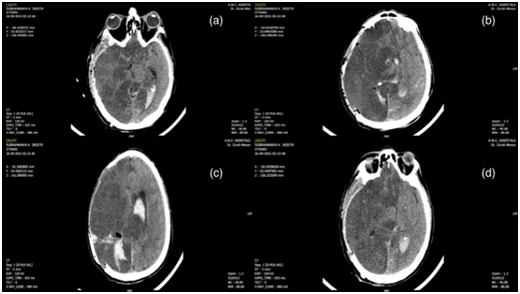

A 73-year-old diabetic, hypertensive male presented with the history of sudden onset altered sensorium and left sided weakness. On admission, nearly 4 hours after the ictus, he was intubated and had a Glasgow Coma Scale (GCS) of E1M3 with pupillary asymmetry, right pupil being larger. His blood pressure was high on admission (200/120mm of Hg) and his blood sugars were 236gm%. His Computed tomographic scan of the (CT) brain showed a massive right-sided parieto-occipital bleed with intraventricular extension and early hydrocephalus along with diffuse oedema (Figure 1). (SICH score 5). After explaining the pros and cons of intervention, he was taken up for evacuation of the haematoma under GA. As the brain remained full even after clot evacuation the bone flap was not replaced and a lax duroplasty was done. Preoperatively he remained stable with no major hemodynamic fluctuations. His blood pressures were maintained around a MAP of 100-120 mm of Hg as is the unit protocol. He was electively ventilated and started on decongestants. Postoperative CT scan done on day1 showed a large right ICA infarct with mass effect and midline shift (Figure 2). Thereafter he continued to deteriorate in spite of full cerebral protective measures and eventually succumbed 3 days after surgery.

Figure 1 Preoperative axial CT Scans showing a large right parieto-occipital haematoma with intraventricular extension and early hydrocephalus (a to d).